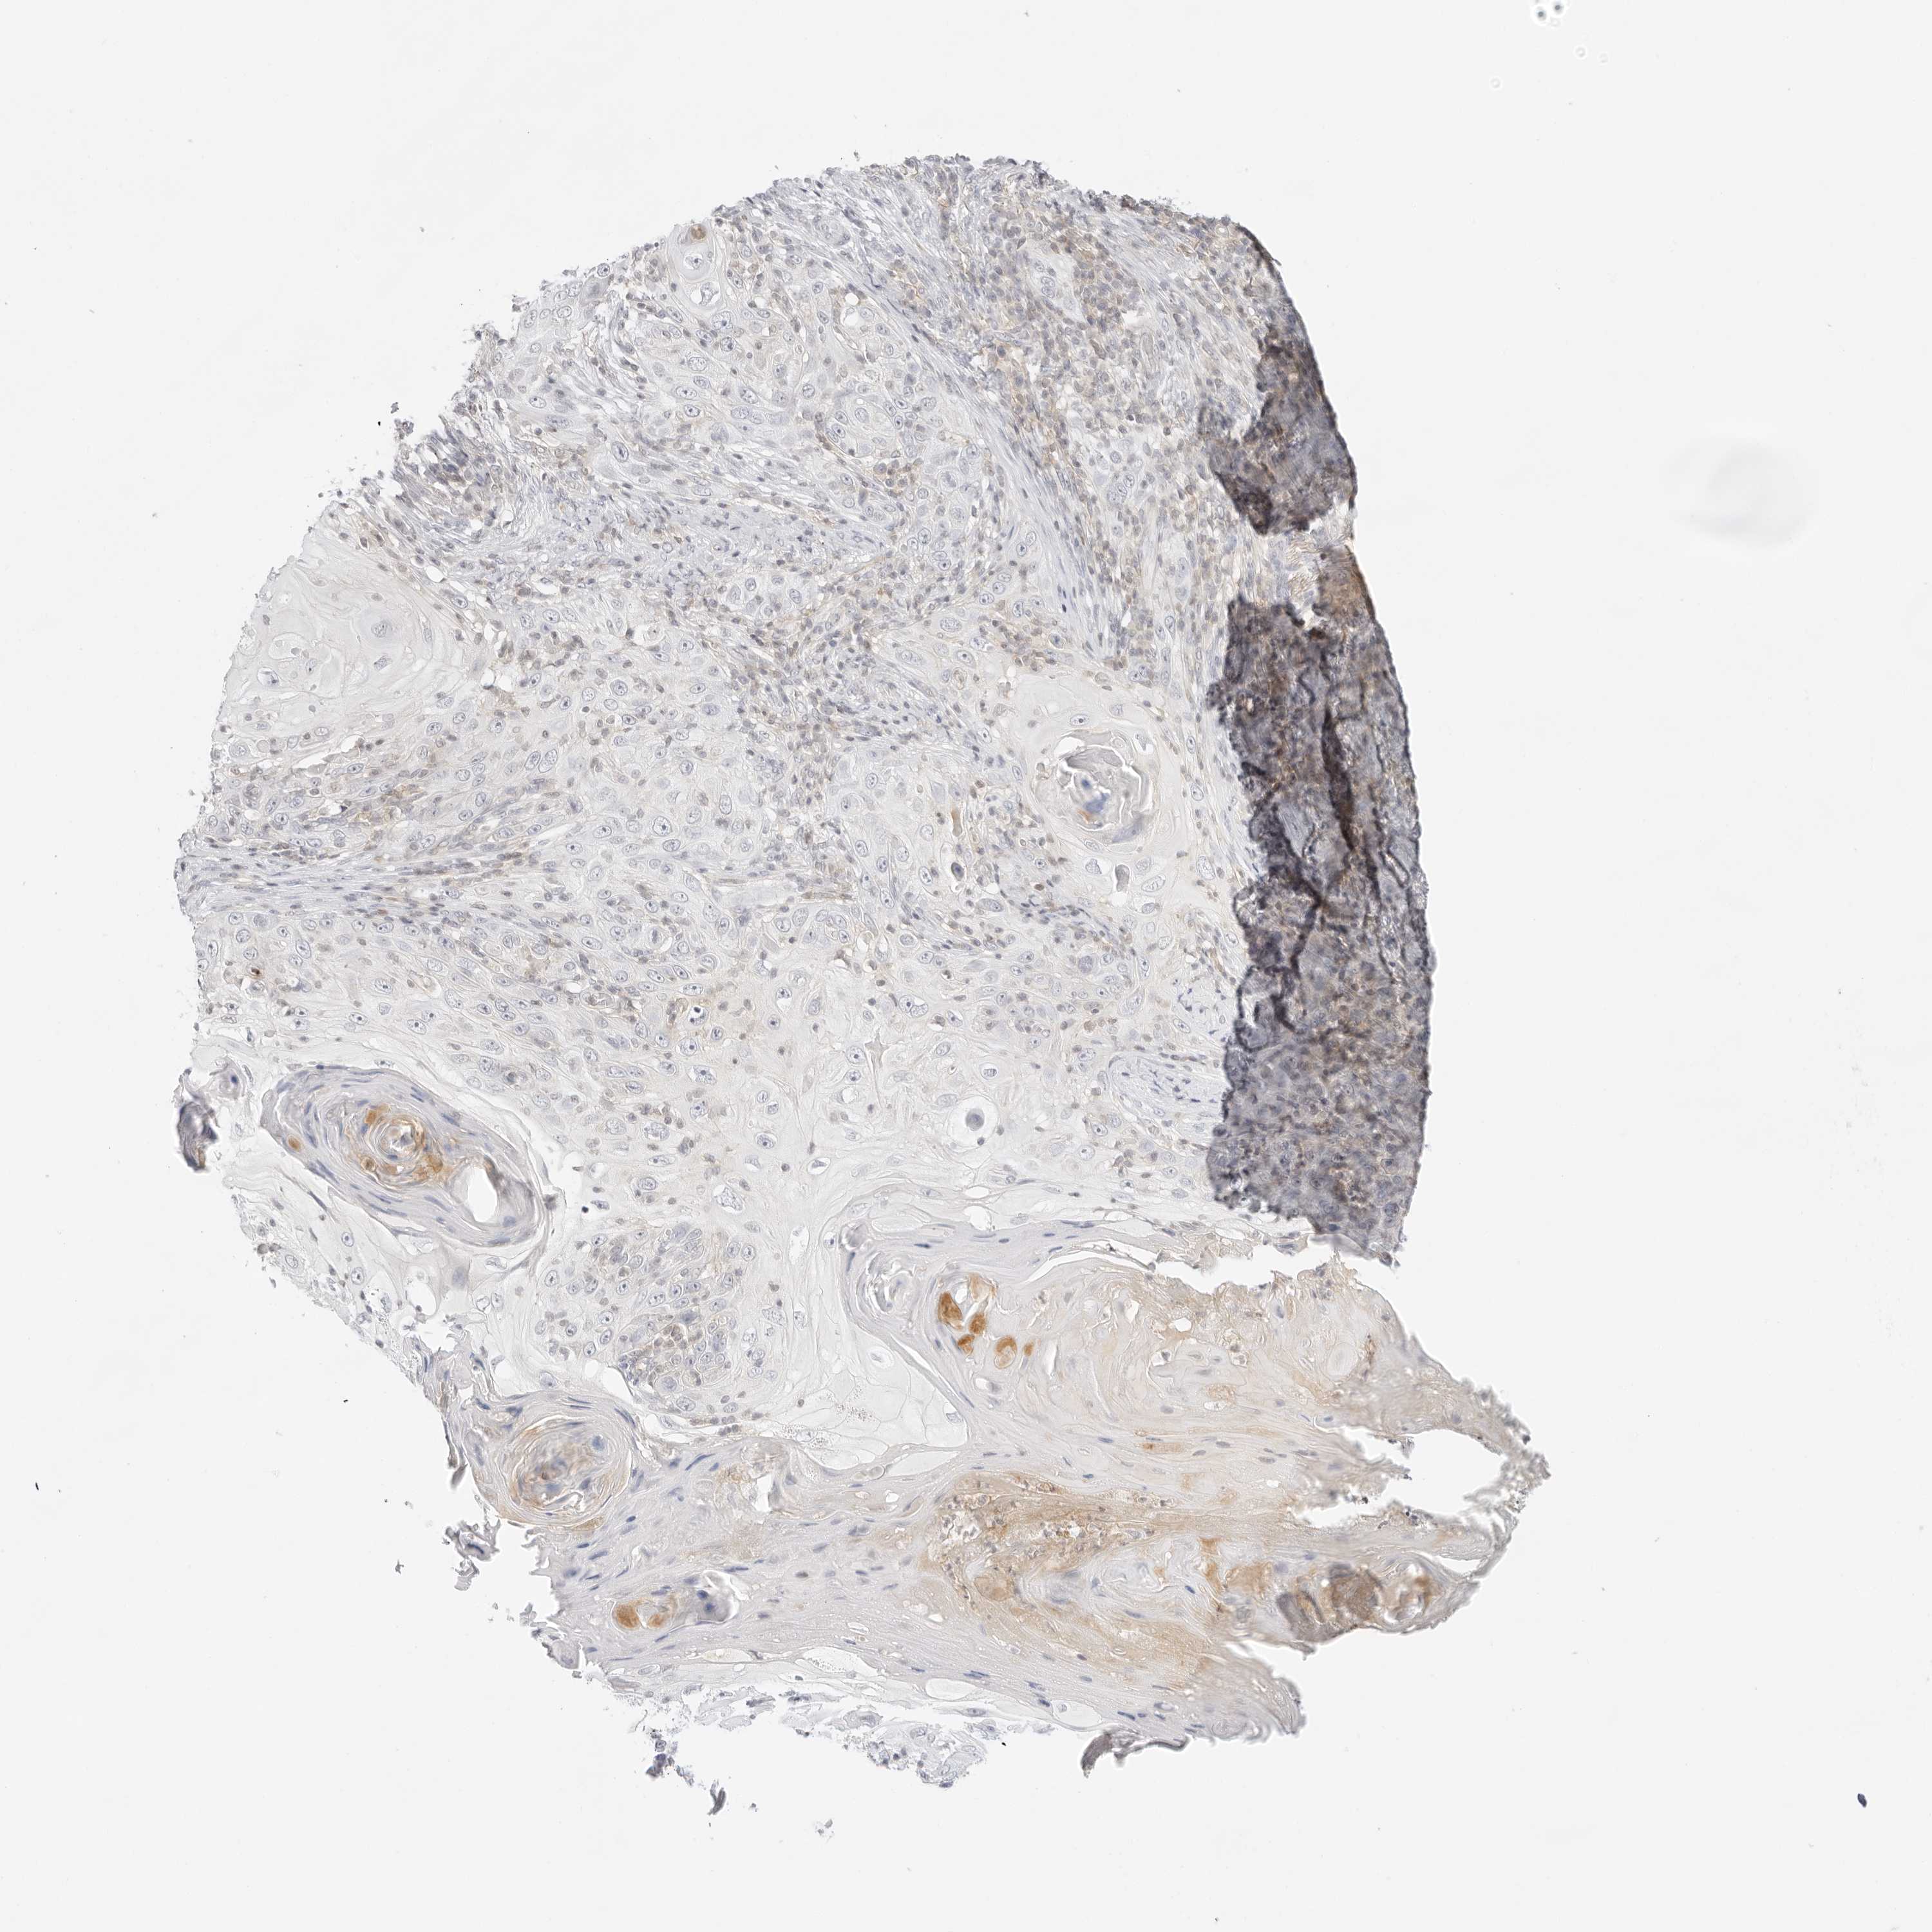

SKIN CANCER - Protein expressioni

A mouse-over function shows sample information and annotation data. Click on an image to view it in a full screen mode. Samples can be filtered based on level of antibody staining by selecting one or several of the following categories: high, medium, low and not detected. The assay and annotation is described here.

Antibody stainingi

Antibody staining in the annotated cell types in the current human tissue is reported as not detected, low, medium, or high, based on conventional immunohistochemistry profiling in selected tissues. This score is based on the combination of the staining intensity and fraction of stained cells.

Each image is clickable and will lead to virtual microscopy that enables deeper exploration of all samples and also displays staining intensity scores, fraction scores and subcellular localization as well as patient and tissue information for each sample.

Antibody CAB030007

Squamous cell carcinoma, NOS

Squamous cell carcinoma, metastatic, NOS